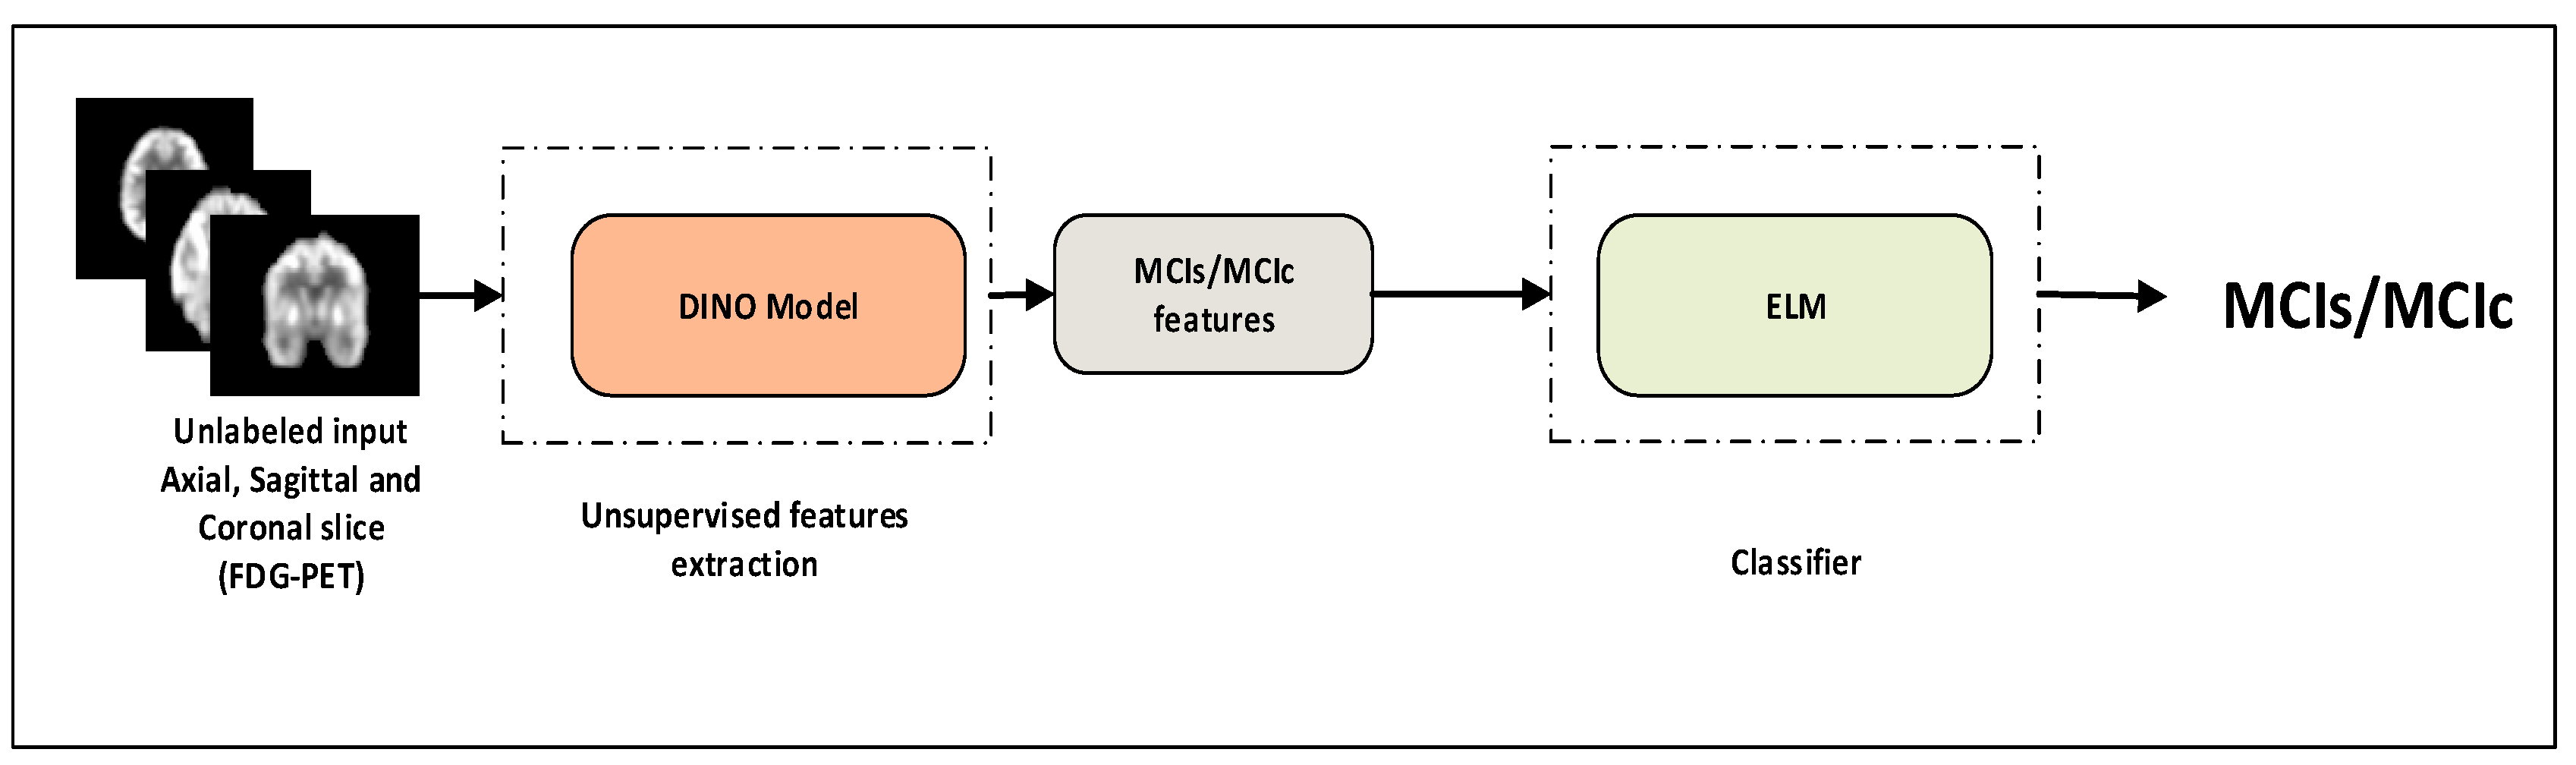

- A transformer model is suggested for the identification of MCI progression. The model expands upon the ViT backbone by utilizing 18F-FDG-PET and self-supervised learning to tackle the issue of MCI progression and disease identification.

- To address the issue of inadequate data in the field of brain imaging, we suggested a cross-domain transfer learning technique. We used ViT as the backbone with DINO.

- In the MCI recognition, experimental data show that the proposed method can achieve more competitive outcomes than current models. The model accuracy levels with the ADNI dataset were 92.31%, which is higher than the baseline’s ViT approach. Finally, we visualized important metabolic brain regions, which can assist the physician for proper analysis of MCI.

2.5. 18F-FDG-PET Feature Learning with ViT-Dino

2.6. Classifiers